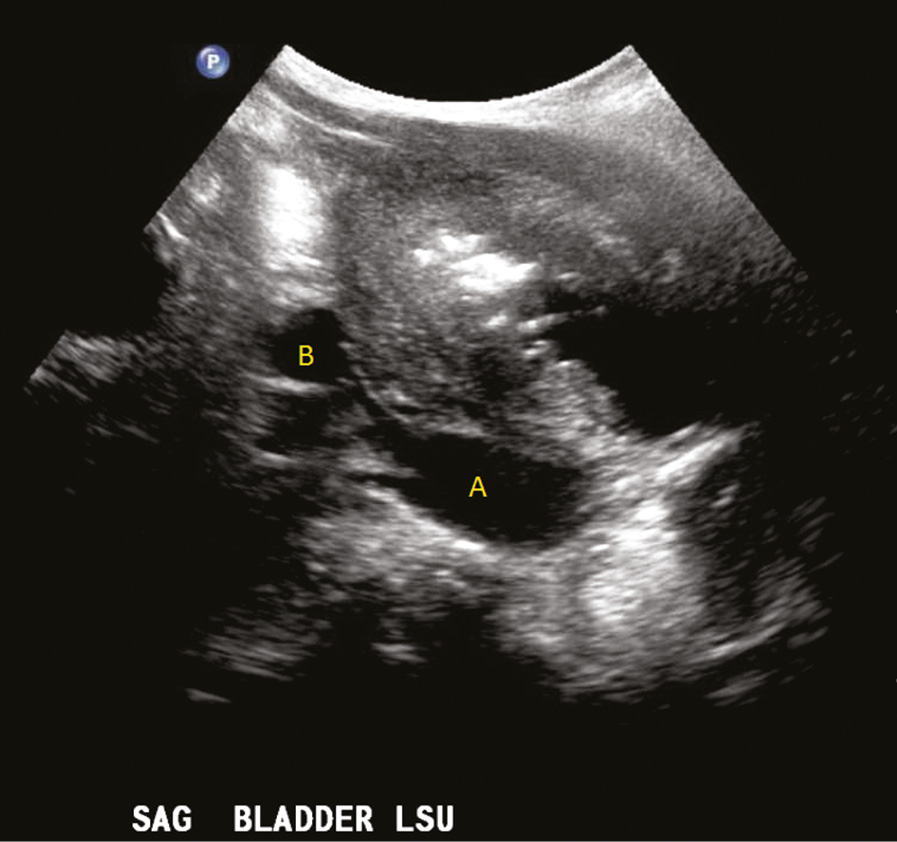

Specific Newborn and Infant Procedures (Section 3) - Essentials of Anesthesia for Infants and Neonates

Specific Newborn and Infant Procedures (Section 3) - Essentials of Anesthesia for Infants and Neonates

PDF) The Febrile Infant: What's New?

Specific Newborn and Infant Procedures (Section 3) - Essentials of Anesthesia for Infants and Neonates